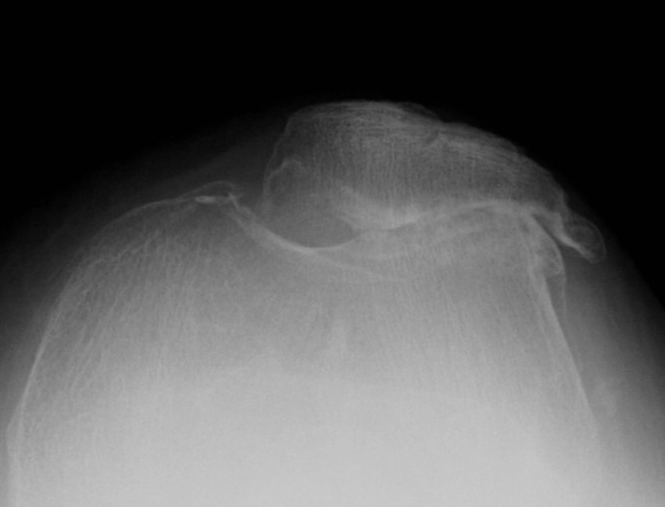

X-ray

Narrowing / osteophytes / sclerosis

Tilt / subluxation

Tilt Subluxation / osteophytes